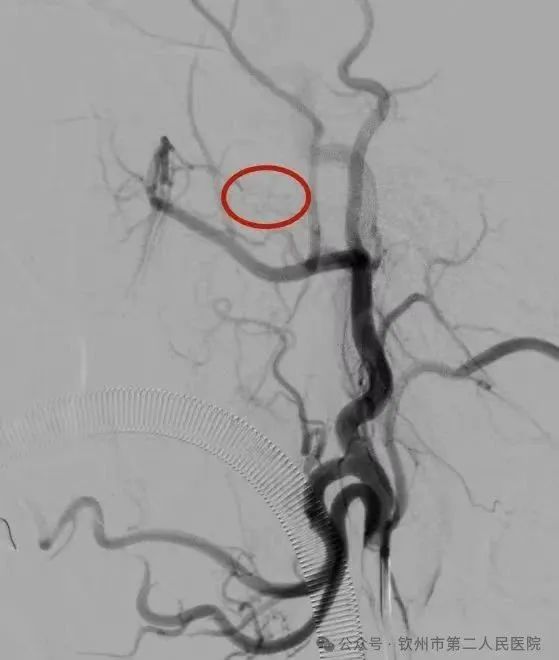

神经介入科副主任彭富考虑此次鼻出血因鼻咽癌侵犯动脉导致,建议立即行介入栓塞治疗。经过沟通,患者及其家属决定行介入栓塞治疗。随后,立即紧急启动绿色通道,送介入手术室急诊行介入手术止血。术中血管造影提示右侧颈外动脉咽外动脉分支可见活动性出血,由此“犯罪血管”被找到。通过直径头发丝大小的微导管送入“犯罪血管”进行生物胶精准栓塞,造影下见“犯罪血管”闭塞,出血停止。整个过程,只有股动脉的穿刺入路的穿刺口,创伤极少,恢复快,效果好。